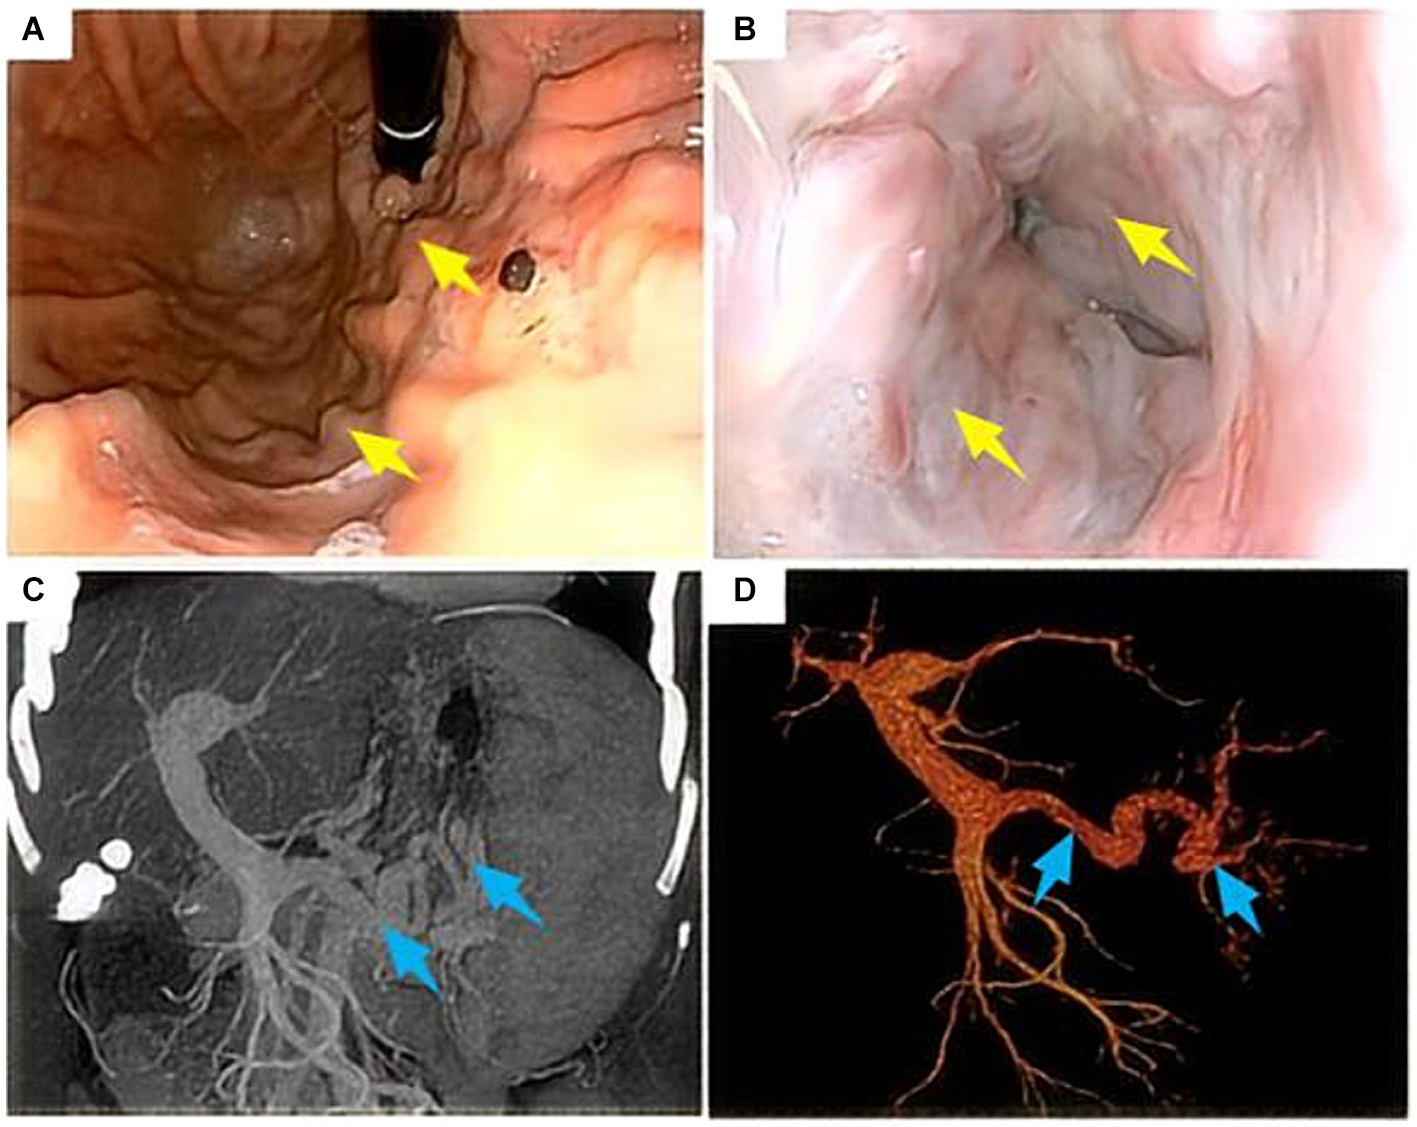

Combining the patient’s medical history and clinical auxiliary examination results, we attributed the patient’s repeated hematemesis to a portal hypertension caused by liver cirrhosis, resulting in upper gastrointestinal bleeding. The patient’s main request is for treatment of upper gastrointestinal bleeding. After completing the preoperative examinations to rule out surgical contraindications, the patient underwent robot-assisted LSPD under general anesthesia on July 30, 2021 (operation duration, 5 h and 15 min; intraoperative bleeding, 800 mL including 600 mL of splenic blood; intraoperative infusion, 800 mL of suspended red blood cells, 600 mL of plasma, and 400 mL of platelets). After the operation, the patient was given intensive respiratory, circulatory, and coagulation function monitoring, gastrointestinal decompression, infection prevention, liver protection, inhibition of gastric acid secretion, and nebulization/inhalation therapy. On the fourth postoperative day, the patient suddenly felt chest tightness and underwent a chest CT, which showed bilateral pleural effusions, atelectasis in most of the lower lobes of both lungs, and a small amount of pericardial effusion (Figure 2A). The patient underwent ultrasound-guided percutaneous right pleural effusion puncture, and the puncture fluid was a clear, pale yellow liquid with a negative chyle test (−). After the puncture, the daily drainage volume was approximately 200 mL, and the patient continued to receive the previous treatment, in addition to antiviral therapy. Eight days after the operation, CT reexamination images showed that the bilateral pleural effusions had decreased (Figure 2B). Continued symptomatic supportive treatment resulted in a stable condition and improved mental state on the 11th post-operative day. The chest drainage tube was removed and the patient was discharged.

Figure 2. A 47-year-old female patient underwent obot-assisted laparoscopic splenectomy combined with pericardial devascularization (LSPD). (A) Chest CT 4 days after LSPD showed bilateral pleural effusions and most of the lower lobes of both lungs were atelectatic (white arrows); (B) percutaneous percutaneous drainage of the right pleural effusion was performed, and a follow-up CT 8 days after the operation showed a decrease in the bilateral pleural effusions (red arrows); (C) Chest CT 47 days after the operation showed a small amount of effusion in the right pleural cavity (yellow arrow); (D) The mediastinal window of the chest CT on day 116 postoperatively showed a large right pleural effusion, complete atelectasis of the right lung, and left shift of the trachea, heart, and mediastinum (red arrow); (E) the patient underwent percutaneous right pleural effusion puncture and drainage, and chest CT on day 129 postoperatively still showed a large right pleural effusion (yellow arrow); (F) chest CT on day 137 postoperatively showed a large right pleural effusion but less than before (blue arrow).

After discharge, the patient recovered smoothly. Later, 47 days after the LSPD, chest CT images showed only a small amount of right-sided pleural effusion (Figure 2C). At 116 days after the LSPD, the patient experienced severe coughing and felt chest tightness and shortness of breath. Chest CT reexamination showed a large amount of right-sided pleural effusion, complete atelectasis of the right lung, and left displacement of the trachea, heart, and mediastinum (Figure 2D). The patient was admitted to the hepatobiliary surgery department again for an ultrasound-guided thoracentesis. The puncture fluid was milky white and turbid, and the chylous test result was positive (+). The daily drainage volume after puncture was approximately 1,500 mL. At this time, the patient’s liver function was still normal [total bilirubin (TBIL), 8.6 μmol/L; alanine aminotransferase (ALT), 18 U/L; aspartate transaminase (AST), 18 U/L; albumin (ALB), 42.3 g/L]. However, 129 days after the LSPD, the chest CT images still showed a large right-sided pleural effusion (Figure 2E). The patient developed hypoalbuminemia (ALB, 31.4 g/L) and moderate peritoneal effusion, which was considered related to the chylothorax. Liver protection, hypoalbuminemia correction, moderate diuresis, nutritional support, and other treatments were continued. The daily drainage volume of chest drainage fluid decreased to approximately 1,000 mL, and the amount of peritoneal effusion decreased gradually. On postoperative day 137, a chest CT showed a large pleural effusion on the right side that was smaller than the previous one (Figure 2F). Conservative treatment was continued with fasting, nutritional support, continuous chest drainage, and intrathoracic injection of pingyangmycin (16 mg of pingyangmycin +10 mg of dexamethasone, chest injection, 5–7 days/time, continuous treatment for 3 times) taking into consideration the massive chylothorax of the patient. However, the effect was poor, and the chest drainage fluid increased to approximately 4,000 mL/day. The drainage fluid was a milky white turbid liquid, and the chyle test was positive (+).

We thought the large right-sided chylothorax was probably associated with the liver cirrhosis, portal hypertension, increased lymphatic fluid production, and lymphatic vessel ruptures. Therefore, we once again excluded surgical contraindications, and the patient underwent ultrasound-guided left lymph node imaging through the inguinal region to identify the location of the chylous fistula. The imaging results showed normal morphology and lymphatic vessels course in the pelvic and lumbar segments, and we found no significant fistulas in the thoracic segment (Figure 3A). Compared with the preoperative LSPD, the portal vein width had increased from 1.58 cm to 1.7 cm (Figure 3B). After a multidisciplinary consultation meeting (thoracic surgery, cardiovascular medicine, interventional therapy room, digestive medicine, and hepatobiliary surgery), we agreed that a trans-jugular intrahepatic portosystemic shunt (TIPS) would be used to reduce the portal pressure and alleviate the lymphatic reflux and the chylothorax. We communicated with the patient’s family and obtained a signed surgical consent form, the patient underwent TIPS under general anesthesia on day 169 after the initial LSPD (Figure 3C). During the procedure, the portal pressure decreased from 40 cm of water column before surgery to 30 cm of water column after the surgery. In addition, we found irregular filling defects in the main portal vein and left and right branches of the portal vein that appeared to be thrombosis lesions (Figure 3C). On days 1, 2, and 3 after the TIPS operation, the chest drainage tube fluid volumes were 700 mL, 800 mL, and 750 mL, respectively. After therapy for liver protection, electrolyte imbalance correction, anti-infection, and other symptomatic treatments, the chest CT images showed improvement in the right-sided pleural effusion compared with the pre-operative findings (Figure 4A). On day 14 after the TIPS, chest CT images showed a small pleural effusion on the right side and local thickening and adhesion of the bilateral pleuras (Figure 4B). The patient’s chest drainage tube fluid decreased to 50 mL 18 days after the TIPS operation, and the chest drainage tube was removed. The patient was discharged 20 days after the TIPS operation and has been followed up for 2 years without recurrence of gastric variceal bleeding or chylothorax. The patient signed a written informed consent for the publication of the data in this case report.

Figure 3. A 47-year-old female patient underwent robot-assisted LSPD. (A) 165 days after LSPD, ultrasound-guided lymphangiography through the inguinal region showed no abnormalities in the shape of the pelvic and lumbar lymphatic vessels, and no visualization of the thoracic lymphatic vessels (red arrows); (B) Compared with the pre-LSPD, the portal vein width before TIPS increased from 1.58 cm to 1.7 cm (yellow arrow); (C) During TIPS treatment, thrombosis in the portal vein was found. The patient underwent TIPS treatment under general anesthesia 169 days after LSPD (blue arrow).

Figure 4. A 47-year-old female patient underwent robotic assisted LSPD, TIPS treatment was performed 169 days after LSPD surgery. (A) On the 4th day after TIPS surgery, a chest CT scan (chest window) showed a small amount of pleural effusion on the right side, which was significantly improved compared to before (red arrow); (B) 14 days after TIPS surgery, chest CT showed no obvious effusion in the right chest cavity and good lung expansion (yellow arrow); (C,D) The patient’s serum alanine aminotransferase (ALT) level and chest drainage fluid decreased significantly after TIPS.